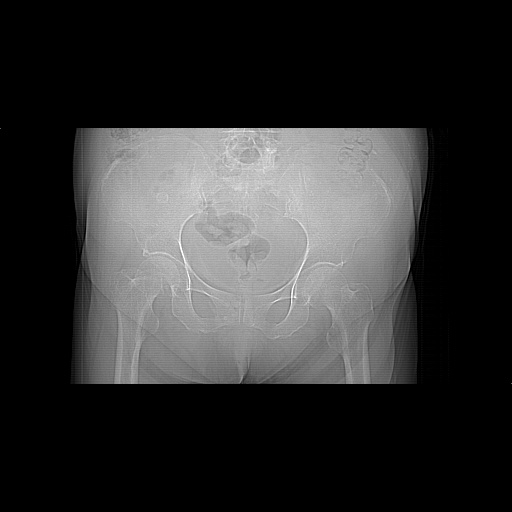

患者,女,74岁,无不适,b超示盆腔包块。

子宫前上方巨大脂性肿物,肿物边缘为较厚软组织密度影,其内缘欠光整,脂性密度中央见结节状软组织密度影“漂浮”,肿物与子宫前壁关系密切,考虑1脂肪瘤2皮样囊肿3肌瘤脂样变